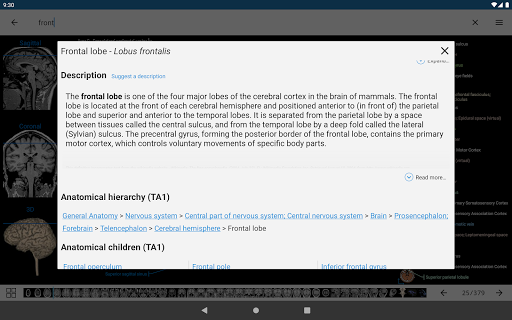

*Visibilidad mejorada de las definiciones de partes anatómicas

. *Navegación entre partes anatómicas usando enlaces de descripción.

la vista de detalles de una estructura anatómica ahora se muestran los términos relacionados